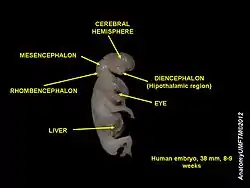

During embryonic development, the midbrain (also known as the mesencephalon) arises from the second vesicle of the neural tube, while the interior of this portion of the tube becomes the cerebral aqueduct. Unlike the other two vesicles – the forebrain and hindbrain – the midbrain does not develop further subdivision for the remainder of neural development. It does not split into other brain areas. while the forebrain, for example, divides into the telencephalon and the diencephalon.[13]

Throughout embryonic development, the cells within the midbrain continually multiply; this happens to a much greater extent ventrally than it does dorsally. The outward expansion compresses the still-forming cerebral aqueduct, which can result in partial or total obstruction, leading to congenital hydrocephalus.[14] The tectum is derived in embryonic development from the alar plate of the neural tube.